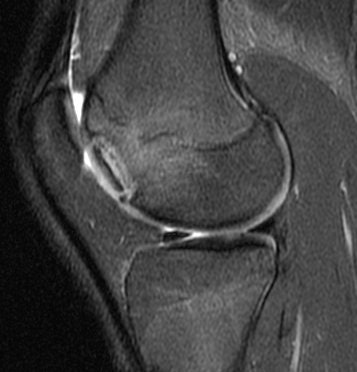

![]() |

| Sagittal MRI of JOCD on 1.5-tesla scanner. Protocol included FSE and T2-weighted imaging (TR/TE 3500/55). Image courtesy of Dr. Nancy Major, Duke University Medical Center, Durham, NC. |